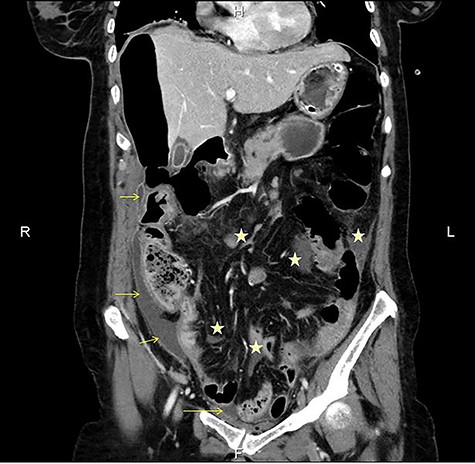

CT multiplanar reconstruction (upper level, supine position) shows free air in continuity with intraluminal (duodenum) air. Notice the presence of free fluid in mesenteric pouches (stars), as well as encapsulated in the right paracolic gutter (arrows) and Douglas space (long arrow).